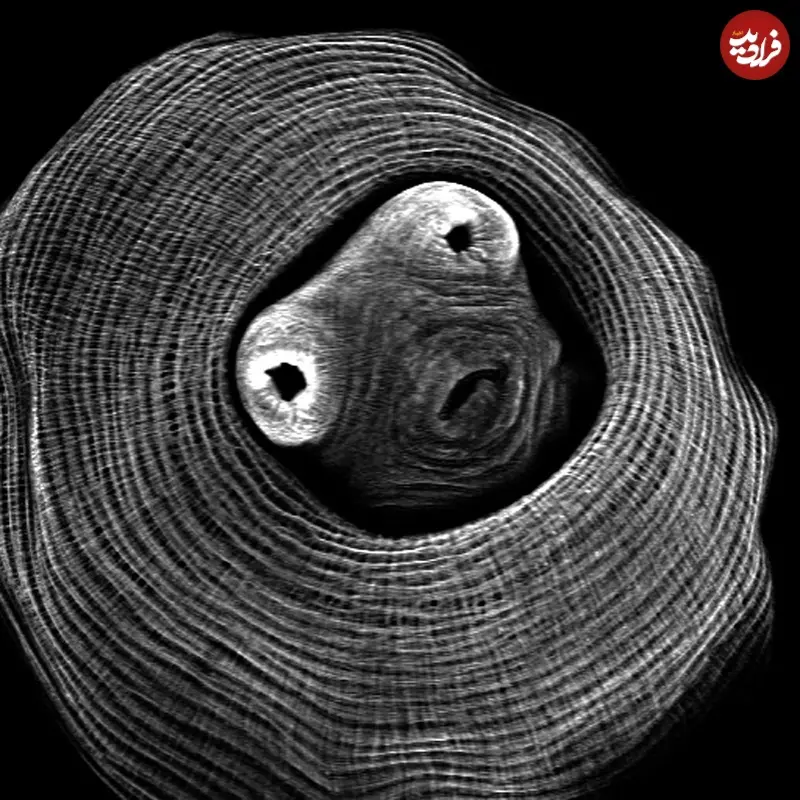

سلولهای عصب بینایی یک جونده